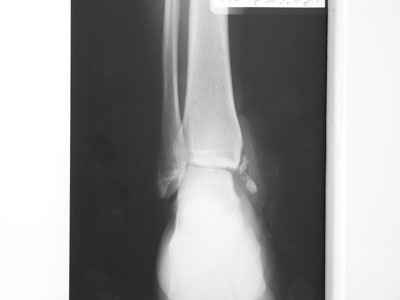

Re: Остеомиелит медиальной лодыжки

Совершенно верно был такой Пациент парень 29 лет. Только не 2 года а 4 года назад. Лечение растянулось на 2 этапа. На момент сообщения наложил окончатую гипсовую повязку, мазевые повязки, грануляции, закрыл свободной кожной пластикой. Через 2 месяца рана закрылась рубцом, гипс снял отправил на ЛФК. В течение года появлялся дважды - все ОК, нестабильности в суставе не было. Пациент работник УВД - его даже не комисовали. Обратился через 2 года после повторной травмы (опять мотоцикл) - открылся свищ в области медиальной лодыжки. Проведена операция - санация, рубец иссечен, пластика суральным лоскутом - состоятельная. Аппарат Илизарова на 2 месяца. Аппарат демонтировали опять ЛФК - Нестабильности в суставе нет, до сих пор трудится в органах... Опять подумывает о покупке мотоцикла.

К сожалению снимки нашел только после пластики. Р-гр где-то утерял посмотрю не работе.